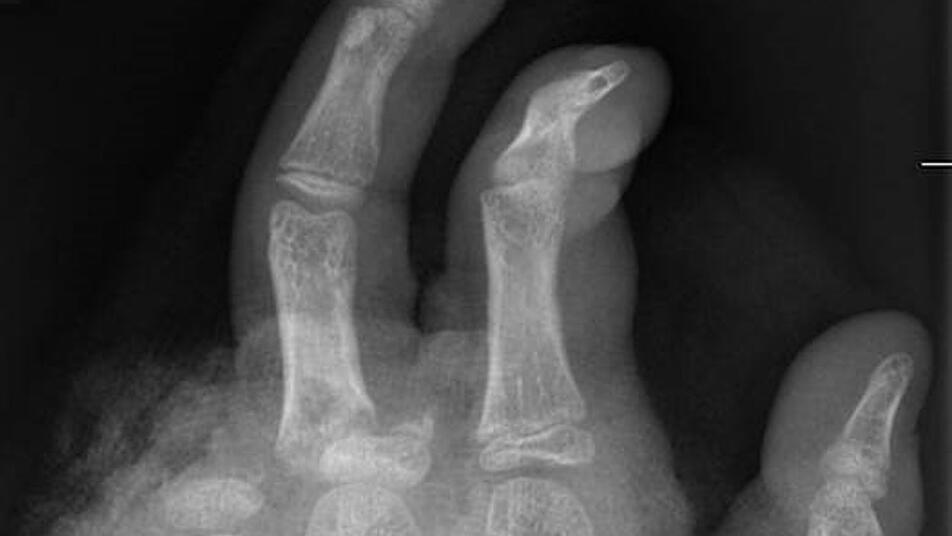

So kann ein Röntgenbild nach einer missglückten Böllerexplosion aussehen: Zwei Finger fehlen.

In der Handchirurgie müssten an Silvester im Unfallkrankenhaus rund 20 bis 40 Menschen mit Böllerverletzungen operiert werden, sagt die Ärztin. Dieses Jahr werde sie mir vier weiteren Handchirurgen im Einsatz sein. Die häufigsten Verletzungen entstünden durch explodierende Böller in der Hand.